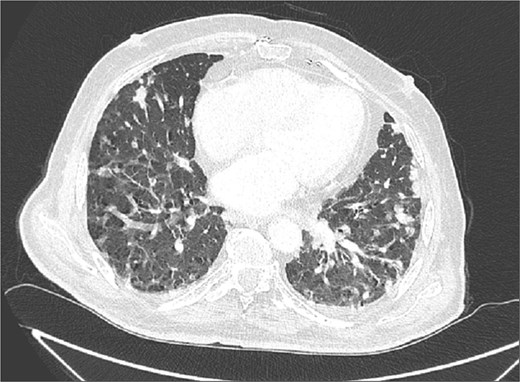

Due to improvement in his symptoms, the patient did not attend his three-month follow-up appointment. Eight months later, the patient was hospitalized with shortness of breath and multiple pulmonary nodules (Fig. 1) on the chest computed tomography (CT) in the pulmonology department of our hospital. Figures 2 and 3 show the preoperative chest X-ray and the chest X-ray taken eight months after the TURP, respectively. Suspected of metastatic disease, a urological evaluation was performed, which revealed an abnormal DRE and a significantly elevated PSA of 134 ng/ml. Diagnostic bronchoscopy and histological findings of the lung biopsy confirmed prostate adenocarcinoma (PCa). TRUS-Bx prostate biopsy (12 cores) confirmed the diagnosis of PCa with involvement of all prostatic cores and Gleason Score (GS) = 8 (4 + 4). Bone scan (Fig. 4) and CT scan were negative for other secondary metastatic lesions in bones and lymph nodes. The patient immediately started combination therapy ADT (degarelix) with apalutamide, and 3 months later, he was off oxygen, and his PSA level had decreased to 14.9 ng/ml.